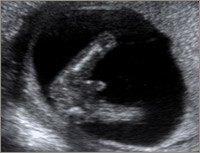

De første 3 billeder er alle uge 15. De to første er dreng og det sidste pige. Det sidste billede er også en pige... Kan derfor godt forstå at hun ikke er helt sikker på kønnet... men tror alligevel jeg tænker dreng

Vedhæftede fotos (klik for at se i fuld størrelse)

Jeg synes jeg kan se en sammenligning mellem dit nummer 2 billede og mit nummer 4 billede (som er en pige) og ellers så synes jeg at jeres ligner mest en dreng...